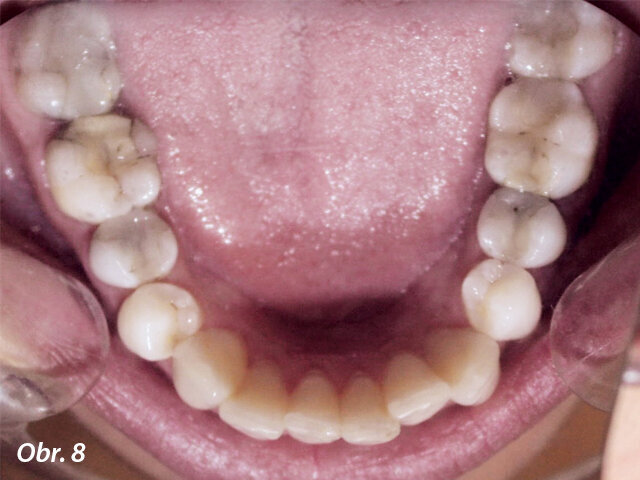

Diagnóza: I. třída Anglea, bialveolární protruze, stěsnání v horním i dolním zubním oblouku.

Byly vyhodnoceny fotografie enface, profil a estetika úsměvu. Pacientka požadovala zlepšení bialveolární protruze (obr. 1–8).

Dále byl vyhodnocen kefalometrický snímek (obr. 9), ortopantomogram (obr. 10) a provedena analýza modelů (obr. 11–15).